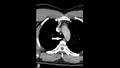

وكشفت الأشعة السينية أنه يعاني من انتفاخ الرئة الجراحي، عندما ينحصر الهواء في أعمق الأنسجة تحت الجلد.

وأظهرت الأشعة المقطعية أن التمزق كان بين العظمتين الثالثة والرابعة من رقبته وأن الهواء يتراكم في الفراغ بين الرئتين في صدره.